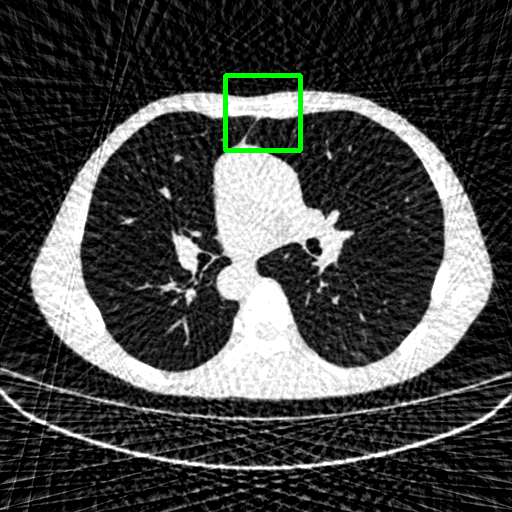

Generalizablity on COVID-19 dataset. Finally, we use slices of another patient in the COVID-19 dataset to test the generalizability of trained models, and quantitative performances are compared in Table 4. ImgTrans and DuDoTrans have achieved a larger improvement about 4-5 dB over CNN-based methods, which shows that the long-range dependency modeling ability helps capture the intrinsic global property of general CT images. Further, our DuDoTrans exceeds ImgTrans about 0.4 dB in all cases, even larger than the original NIH-AAPM dataset. The improvement ensures that DuDoTrans generalizes well to out-of-distribution CT images. Besides, we also show the visualization images in Fig. 5 when = 96. Coinciding with the quantitative comparison, our DuDoTrans show better reconstruction on both global patterns and local details.